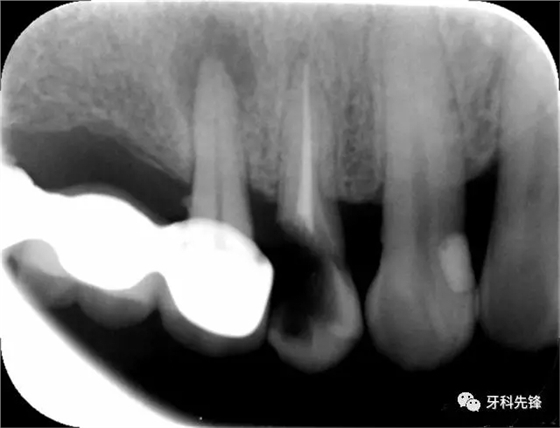

圖1術(shù)前X光片

X 示:15 根管透射,根尖有陰影

14根管阻射,恰填,無(wú)異常

46 根管阻射,恰填,根分叉骨密度降低,近中根尖陰影較大